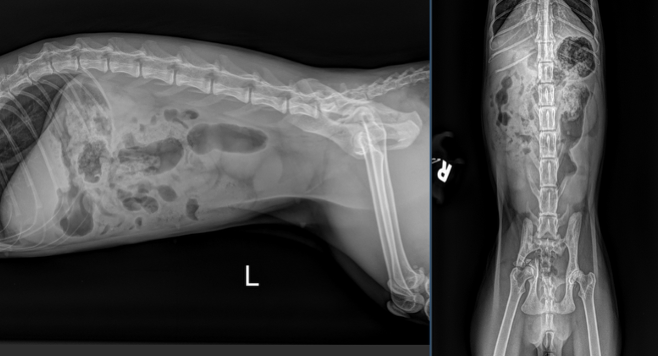

Auffallend im Abdomenröntgen sind runde, homogene, weichteildichte Strukturen, die um die Harnblase lokalisiert sind und sich etwa auf Höhe von L5, sowie L6-7 (pinke Pfeile) befinden. Ihre Ausdehnung entspricht in etwa der Länge eines lumbalen Wirbelkörpers. Im kranialen Abdomen ist das seröse Detail zudem etwas reduziert. Im gesamten Verdauungstrakt findet sich weichteildichtes, teils auch mineraldichtes, granuliertes Material, begleitet von einer moderaten Menge an Luft (exemplarisch mit pinken Pfeilköpfen markiert). Freies abdominales Gas ist nicht nachweisbar und die Harnblase stellt sich intakt dar.

Zusammenfassend ist hervorzuheben, dass es sich bei den weichteildichten Strukturen im kaudalen Abdomen sehr wahrscheinlich um multiple Fruchtblasen in beiden Uterushörnern handelt und somit der hochgradige Verdacht einer Trächtigkeit im Raum steht. Dies sollte unbedingt alsbald ultrasonographisch abgeklärt werden.